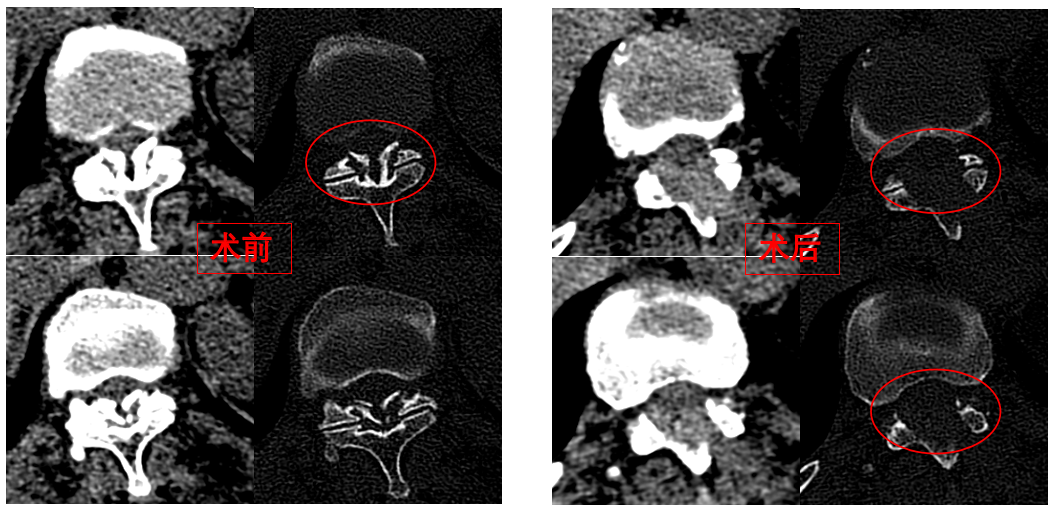

手術(shù)歷時(shí)一個(gè)半小時(shí),骨科脊柱微創(chuàng)團(tuán)隊(duì)成功完整切除了壓迫脊髓的骨化黃韌帶,徹底解除了卓瑪阿媽的脊髓壓迫。手術(shù)過程順利,手術(shù)切口僅1厘米。

圖為卓瑪阿媽術(shù)前、術(shù)后胸椎CT照片對比。